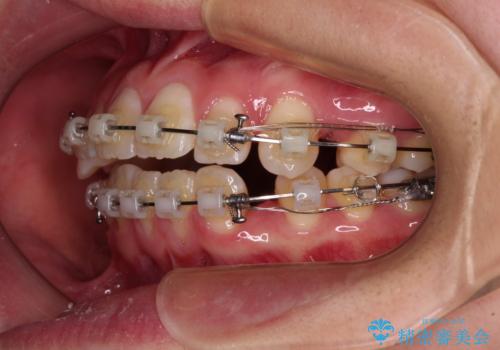

- 矯正装置

- クリアブラケット

口元が引っ込みすぎないようにするために、上下ともに臼歯を前方に移動させる必要があり、インビザラインでは対応できないため、表側のワイヤー装置にて矯正治療を行うこととしました。

口元が引っ込みすぎることもなく、上下前歯がきれいに接触する位置に仕上げることができました。